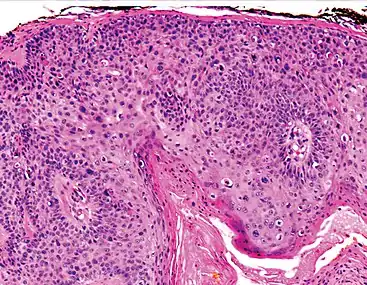

Histopathologically, the epidermis in cSCC in situ (Bowen's disease) will show hyperkeratosis and parakeratosis. There will also be marked acanthosis with elongation and thickening of the rete ridges. These changes will overly keratinocytic cells which are often highly atypical and may in fact have a more unusual appearance than invasive cSCC. The atypia spans the full thickness of the epidermis, with the keratinocytes demonstrating intense mitotic activity, pleomorphism, and greatly enlarged nuclei. They will also show a loss of maturity and polarity, giving the epidermis a disordered or "windblown" appearance.

Two types of multinucleated cells may be seen: the first will present as a multinucleated giant cell, and the second will appear as a dyskeratotic cell engulfed in the cytoplasm of a keratinocyte. Occasionally, cells of the upper epidermis will undergo vacuolization, demonstrating an abundant and strongly eosinophilic cytoplasm. There may be a mild to moderate lymphohistiocytic infiltrate detected in the upper dermis.[12]

Squamous-cell carcinoma in situ, showing prominent dyskeratosis and aberrant mitoses at all levels of the epidermis, along with marked parakeratosis.[12]

Bowen's disease is essentially equivalent to and used interchangeably with cSCC in situ, when not having invaded through the basement membrane.[12] Depending on source, it is classified as precancerous[13] or cSCC in situ (technically cancerous but non-invasive).[47][48] In cSCC in situ (Bowen's disease), atypical squamous cells proliferate through the whole thickness of the epidermis.[12] The entire tumor is confined to the epidermis and does not invade into the dermis.[12] The cells are often highly atypical under the microscope, and may in fact look more unusual than the cells of some invasive squamous-cell carcinomas.[12]

cSCC in situ, high magnification, demonstrating an intact basement membrane.[12]